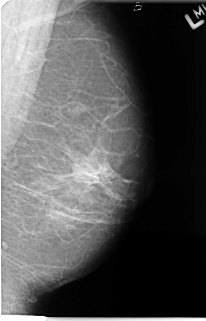

B_3073_1.RIGHT_MLO

FILE: B_3073_1.RIGHT_MLO.OVERLAY

TOTAL_ABNORMALITIES 1

ABNORMALITY 1

LESION_TYPE MASS SHAPE IRREGULAR MARGINS OBSCURED-ILL_DEFINED

ASSESSMENT 3

SUBTLETY 2

PATHOLOGY MALIGNANT